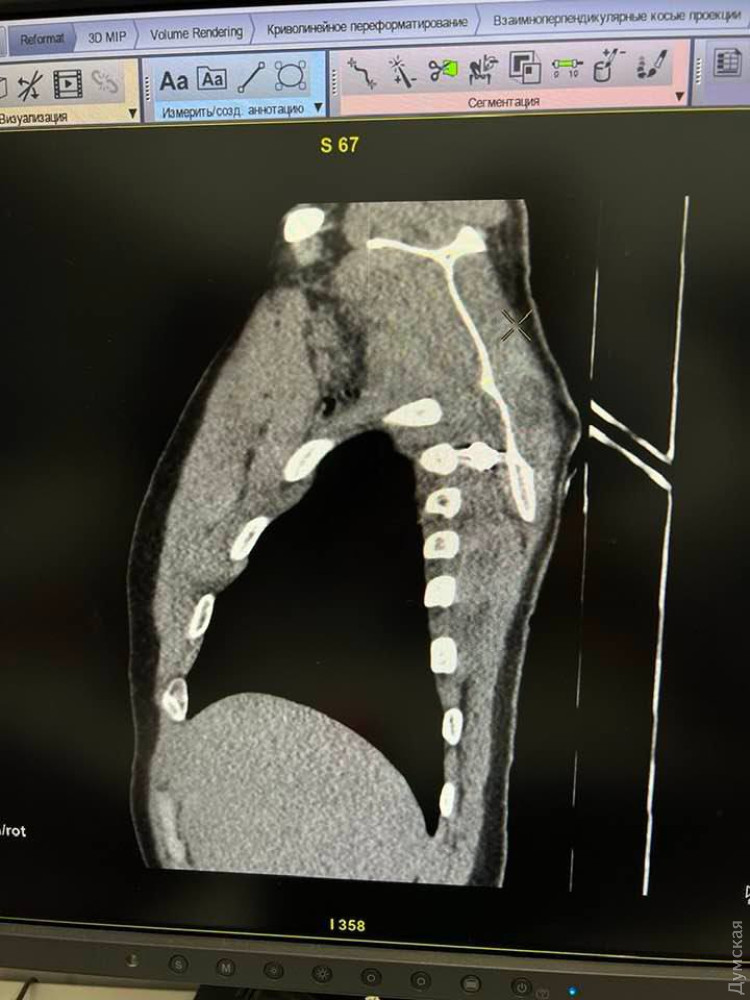

Одеські хірурги провели дві надскладні операції і врятували поранених захисників УкраїниХірурги одеської лікарні провели дві вкрай складні операції з вилучення осколків і врятували життя двох поранених військовослужбовців. Як повідомили «Думській» у медзакладі, 10 лютого операційна бригада витягнула кілька осколків, які перебували біля серця нашого 23-річного захисника. Воїна доправили у важкому стані після поранень, яких він зазнав другого лютого, осколки вдалося виявити під час проведення комп'ютерної томографії. «Уламок дуже близько знаходився до аорти, це велика судина, якою кров іде з серця до всіх частин нашого організму. Навіть транспортувати його могло бути доволі небезпечно, бо цей уламок міг пошкодити аорту і спровокувати величезну втрату крові та смерть. До того ж, як ви бачите на знімку, він був розташований глибоко, тож дійти до нього теж було непросто», — розповіли в лікарні. Операція, яку проводили хірурги Сергій Агєєв, Надім Канжо і Михайло Целіков, пройшла успішно, стан воїна покращився, зараз він продовжує лікування інших поранень. Друга операція відбулася 17 лютого. Із грудної клітки іншого воїна одеські хірурги дістали осколок гранати, повідомили в міській раді. Тепер життю героя нічого не загрожує. СМЕРТЬ РОСІЙСЬКИМ ОКУПАНТАМ! Помітили помилку? Виділяйте слова з помилкою та натискайте control-enter |